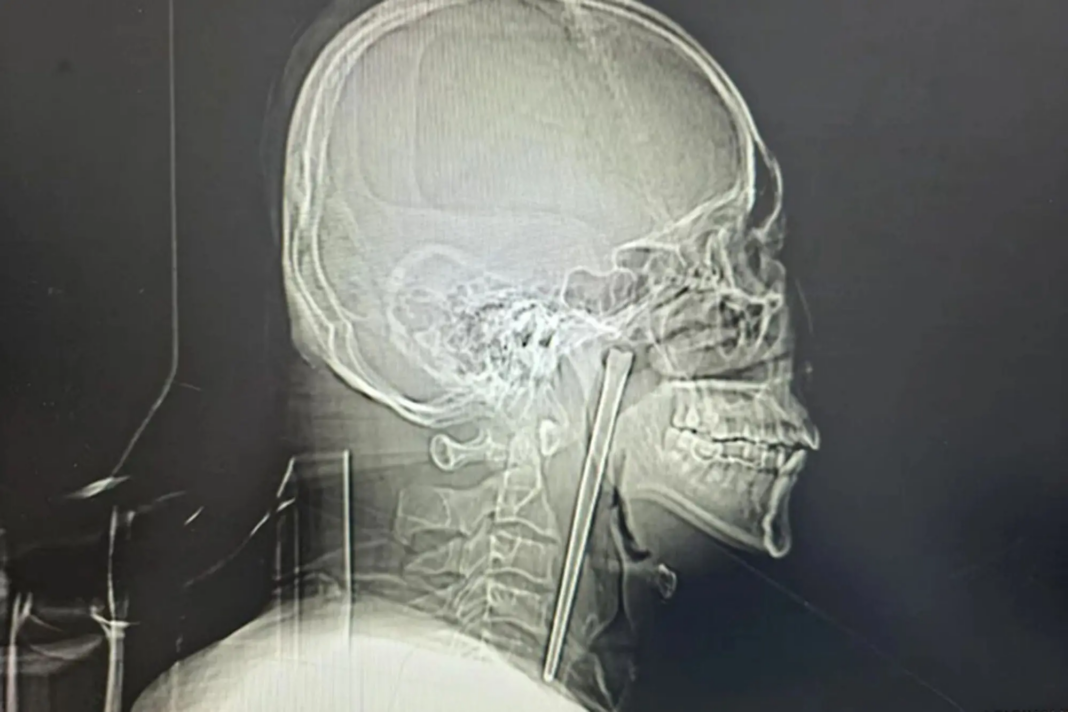

Ο άνδρας, ο οποίος κατονομάζεται μόνο ως κ. Γουάνγκ, πήγε για εξετάσεις λίγο αφότου κατάπιε το ξυλάκι μήκους 13 εκατοστών το 2018, αλλά αρνήθηκε να του το αφαιρέσουν, σύμφωνα με μια μελέτη νοσοκομείου που δημοσιεύθηκε τον Μάρτιο.

Οι χειρουργοί πραγματοποίησαν μια ελάχιστα επεμβατική πράξη για να αφαιρέσουν το αντικείμενο μέσω του στόματος του Γουάνγκ, αντί να κάνουν τομή στον λαιμό του, σύμφωνα με την αναφορά του νοσοκομείου.